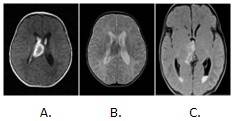

Se decidió realizar estudio complementario con resonancia magnética para confirmar nuestra sospecha y descartar posible lesión ocupativa. (Figura 2).

En contraste con los hallazgos de la RM se decidió realizar tomografía computadorizada para corroborar el diagnóstico. (Figura 3).